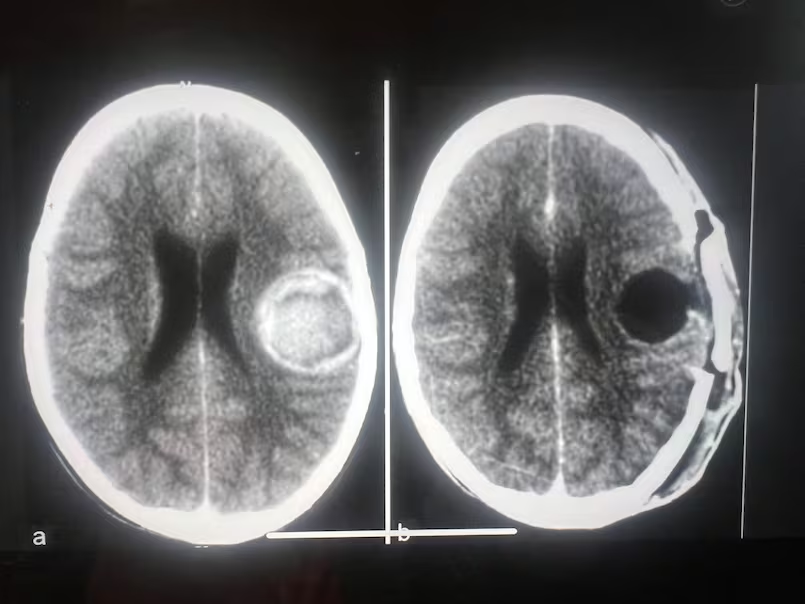

This brain scan image shows Mark Foster’s skull before and after life-saving surgery to remove a cavernoma, an abnormal cluster of thin-walled blood vessels in his brain. The cavernoma existed before his workplace fall but had to be removed after his injury caused brain swelling. (Submitted by Mark Foster)

During that hospital visit, a CT scan showed he had a cavernoma in his brain, an abnormal cluster of thin-walled blood vessels. Some people with cavernomas live normal, healthy lives, unaware they even have them. Foster’s cavernoma wasn’t related to the fall, though it would become significant in the weeks and months after the injury.

He returned to hospital and was told the brain swelling had returned. Doctors decided the cavernoma, about the size of a golf ball, was in the way of his recovery and had to be removed.